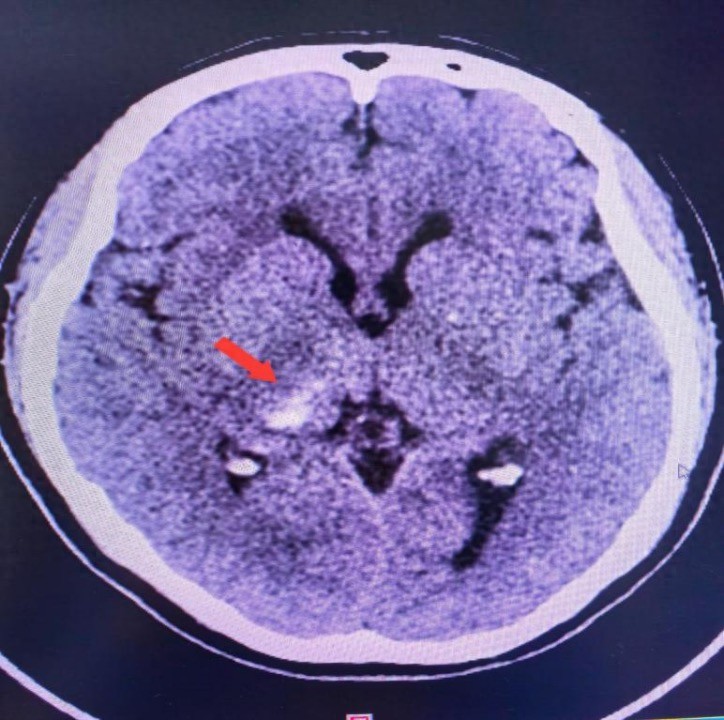

接诊的是脑血管神经外科主任医师刘坤,经过详细检查,发现梁女士脑袋里面竟然出血了……万幸的是梁女士颅内出血量不多。住院期间经精细治疗,排除其它高危因素,加上脑心健康管理师全程管理及宣教,经复查显示颅内出血基本吸收,梁女士痊愈顺利出院。